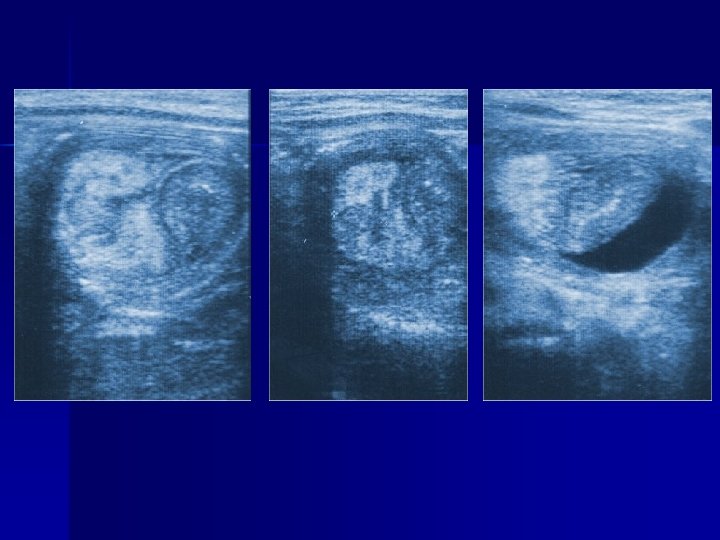

ECOGRAFIA E’ l’esame più utilizzabile nella patologia addominale Possiede: elevata specificità(91 -96%) valore predittivo più elevato versus esame clinico(88>69%).

Ecografia n n E’ una tecnica accurata nell’evidenziare : infiammazioni peri-appendicolari, ileite terminale, adenite mesenterica. invaginazione intestinale patologia testicolare e ginecologica Il limite di questa tecnica è che la qualità della lettura è molto legata alla capacità ed all’esperienza dell’operatore

Cisti ovarica

Torsione ovarica